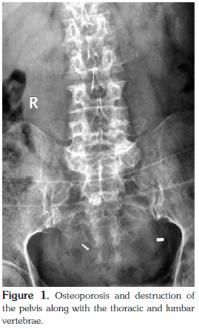

Significant hypergammaglobulinemia was also noted (serum immunoglobulin G (IgG) 32.5 g/l, IgA 0.48 g/l, and IgM <0.18 g/l), and a serum immunoelectrophoretic analysis detected the presence of the kappa-type M protein. The kappa light chain type of Bence-Jones proteinuria was also noted. A biopsy and bone marrow aspiration were performed, and a marrow cytological examination showed a decrease in marrow hyperplasia with rouleau formation, but there was normal morphology of the red blood cells along with plasmacytosis (48%). A pathological examination also revealed a similar result, confirming the diagnosis of MM. In addition, X-rays detected serious osteoporosis and destruction of the pelvis, thoracic vertebrae, and lumbar vertebrae, together with compression fractures of thoracic vertebrae 11 and 12 and lumbar vertebrae 2 and 4 (Figure 1). Moreover, computed tomography showed a lumpy, highly dense shadow in the right hilum and scattered small nodules in the left lung (Figure 2). The patient was then transferred to the Department of Hematology where she underwent chemotherapy with vincristine, doxorubicin, and dexamethasone. Unfortunately, during the third cycle of chemotherapy, the patient died from severe pneumonia.